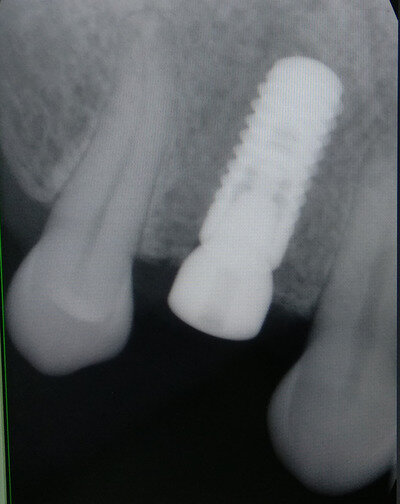

Имплантат